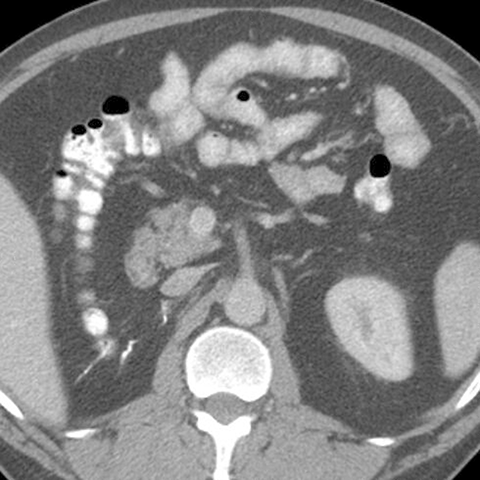

Normal Pancreas, Axial CT [5 of 5]